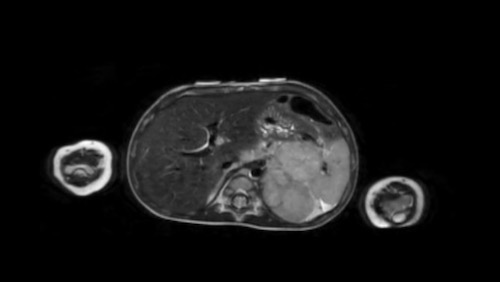

Hình ảnh

Hình ảnh MRI của một bé gái chín tháng tuổi có khối u ở bụng trái. MRI cho thấy khối u tuyến thượng thận trái, một phần đặc, một phần nang. Có nhiều di căn gan.

Khối u đã được sinh thiết. Có tình trạng chảy máu liên tục qua kim dẫn đường. Vào cuối thủ thuật, hai nút bọt gelatin đã được đặt vào (các dải tăng âm (mũi tên)).